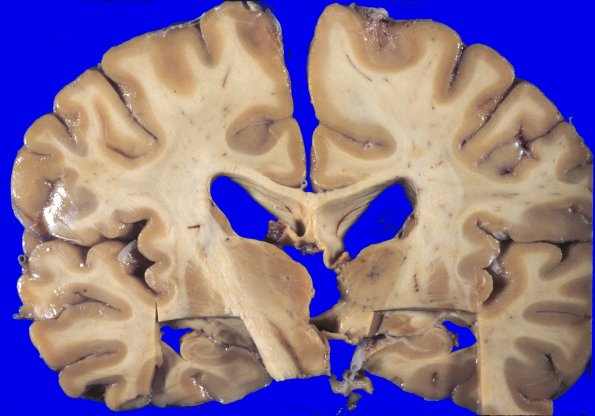

There is modest atrophy of the cerebral hemispheres and dilatation and blunting of the lateral ventricles.